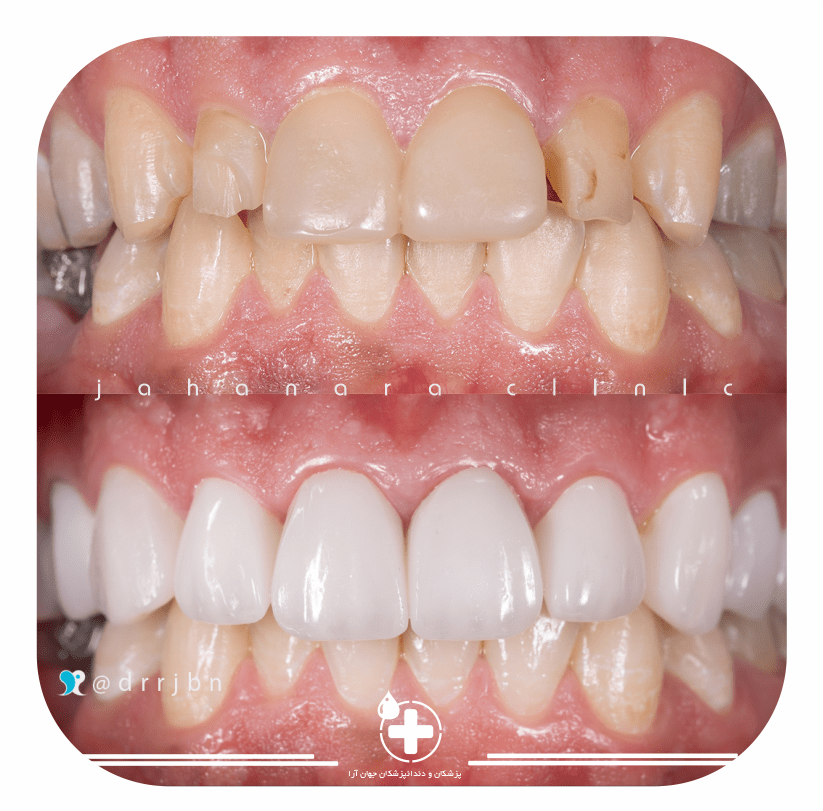

اصلاح طرح لبخند

اصلاح طرح لبخندچون لبخند شما مهم است

لمینت کامپوزیتی و سرامیکی

لمینت کامپوزیتی و سرامیکیاوج کیفیت با امکان مدیریت هزینه